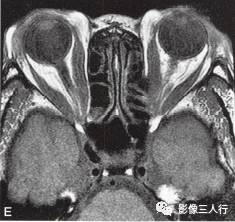

A~C.抑脂T2WI横断面;D~F.T1WI横断面;G~H.T1WI冠状面;I.抑脂T2WI冠状面

横断面显示双侧眼球明显突出,双侧眼球角膜至双侧颧突连线的垂直距离分别为:右侧2.2cm、左侧2.3cm。双侧眼外肌明显增粗,以双侧内、外、上、下直肌明显,短径均可达7mm,且以肌腹增粗明显呈梭形,T1WI等信号(图D~F,图G~H),抑脂T2WI呈明显高信号(图A~C,图I)。双侧眼眶内及球后脂肪增多,双侧眼球内侧至眼眶内侧壁的脂肪厚度增宽。双侧视神经形态及走行正常,双侧眼球晶体、玻璃体形态及信号正常。

影像学检查可帮助该病的诊断与鉴别诊断。CT表现为眼外肌增粗,主要为肌腹增粗,附着于眼球壁上的肌腱不增粗,少数也可同时累及眼外肌肌腹和肌腱。最常累及下直肌,其次为内直肌、上直肌和上提肌,偶尔累及外直肌。MRI表现为受累的眼外肌T1WI低信号,T2WI高信号,压脂T2WI为高信号;晚期眼外肌已纤维化,在T1WI和T2WI均呈低信号。增强扫描急性期时增粗的眼外肌有轻至中度强化,晚期眼外肌纤维化时则无强化。眶内脂肪体积增多表现为球周脂肪尤其是眶前部脂肪的增多。本例影像征象较典型。